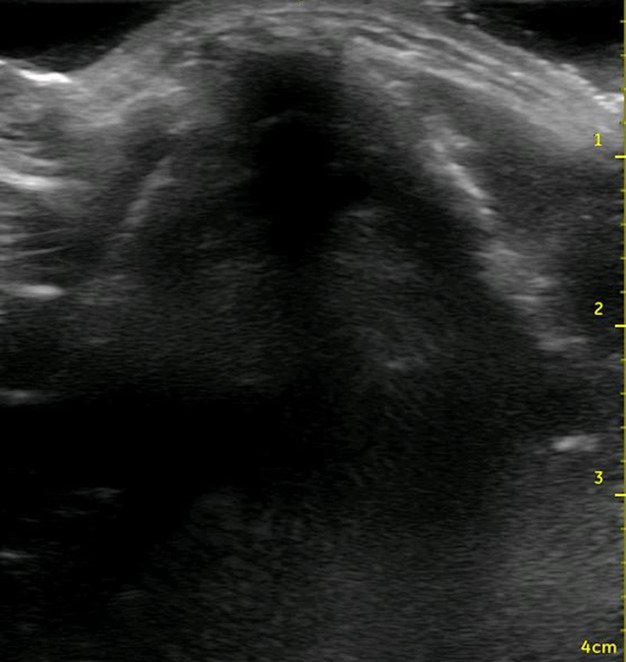

Figure 2. Ultrasound view of the thyroid cartilage in the transverse plane.